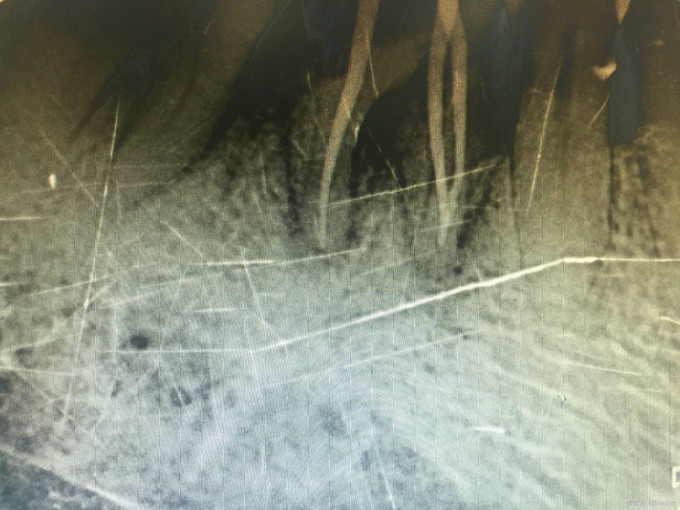

诊断:46牙髓炎 治疗:经患者知情同意后,46局麻去腐降牙合,开髓拔髓寻找根管口,建立直线通路,扩通根管,确定工作长度。S3/EDTA凝胶镍钛器械,低浓度次氯酸钠冲洗根管,预备至25/06,氢氧化钙诊间封药,一周后复诊,试主尖X线示恰充,试干根管,导AH-PLUS糊剂,VDW热压胶垂直加压根充,术后见根管恰充,暂封调合抛光。桩冠修复。